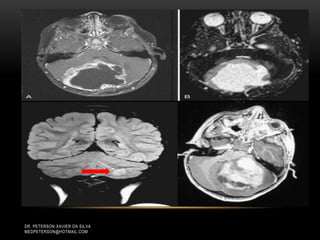

WHO IV Astrocitomas Youmans Proliferação endotelial=> obstrução => isquemia = > necrose DR. PETERSON XAVIER DA SILVA MEDPETERSON@HOTMAIL.COM

WHO IV Astrocitomas Youmans DR. PETERSONXAVIER DA SILVA MEDPETERSON@HOTMAIL.COM Focos Necrose Pseudopalicada Corpo Glomeruloide

WHO IV Astrocitomas Youmans DR. PETERSONXAVIER DA SILVA MEDPETERSON@HOTMAIL.COM Proliferação Endotelial